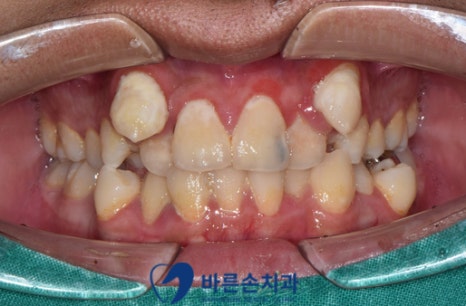

환자분 구강 사진입니다.

전반적으로 구강위생도 잘 되어있지 않았고, 앞니에 까맣게 충치가 생겨있네요.